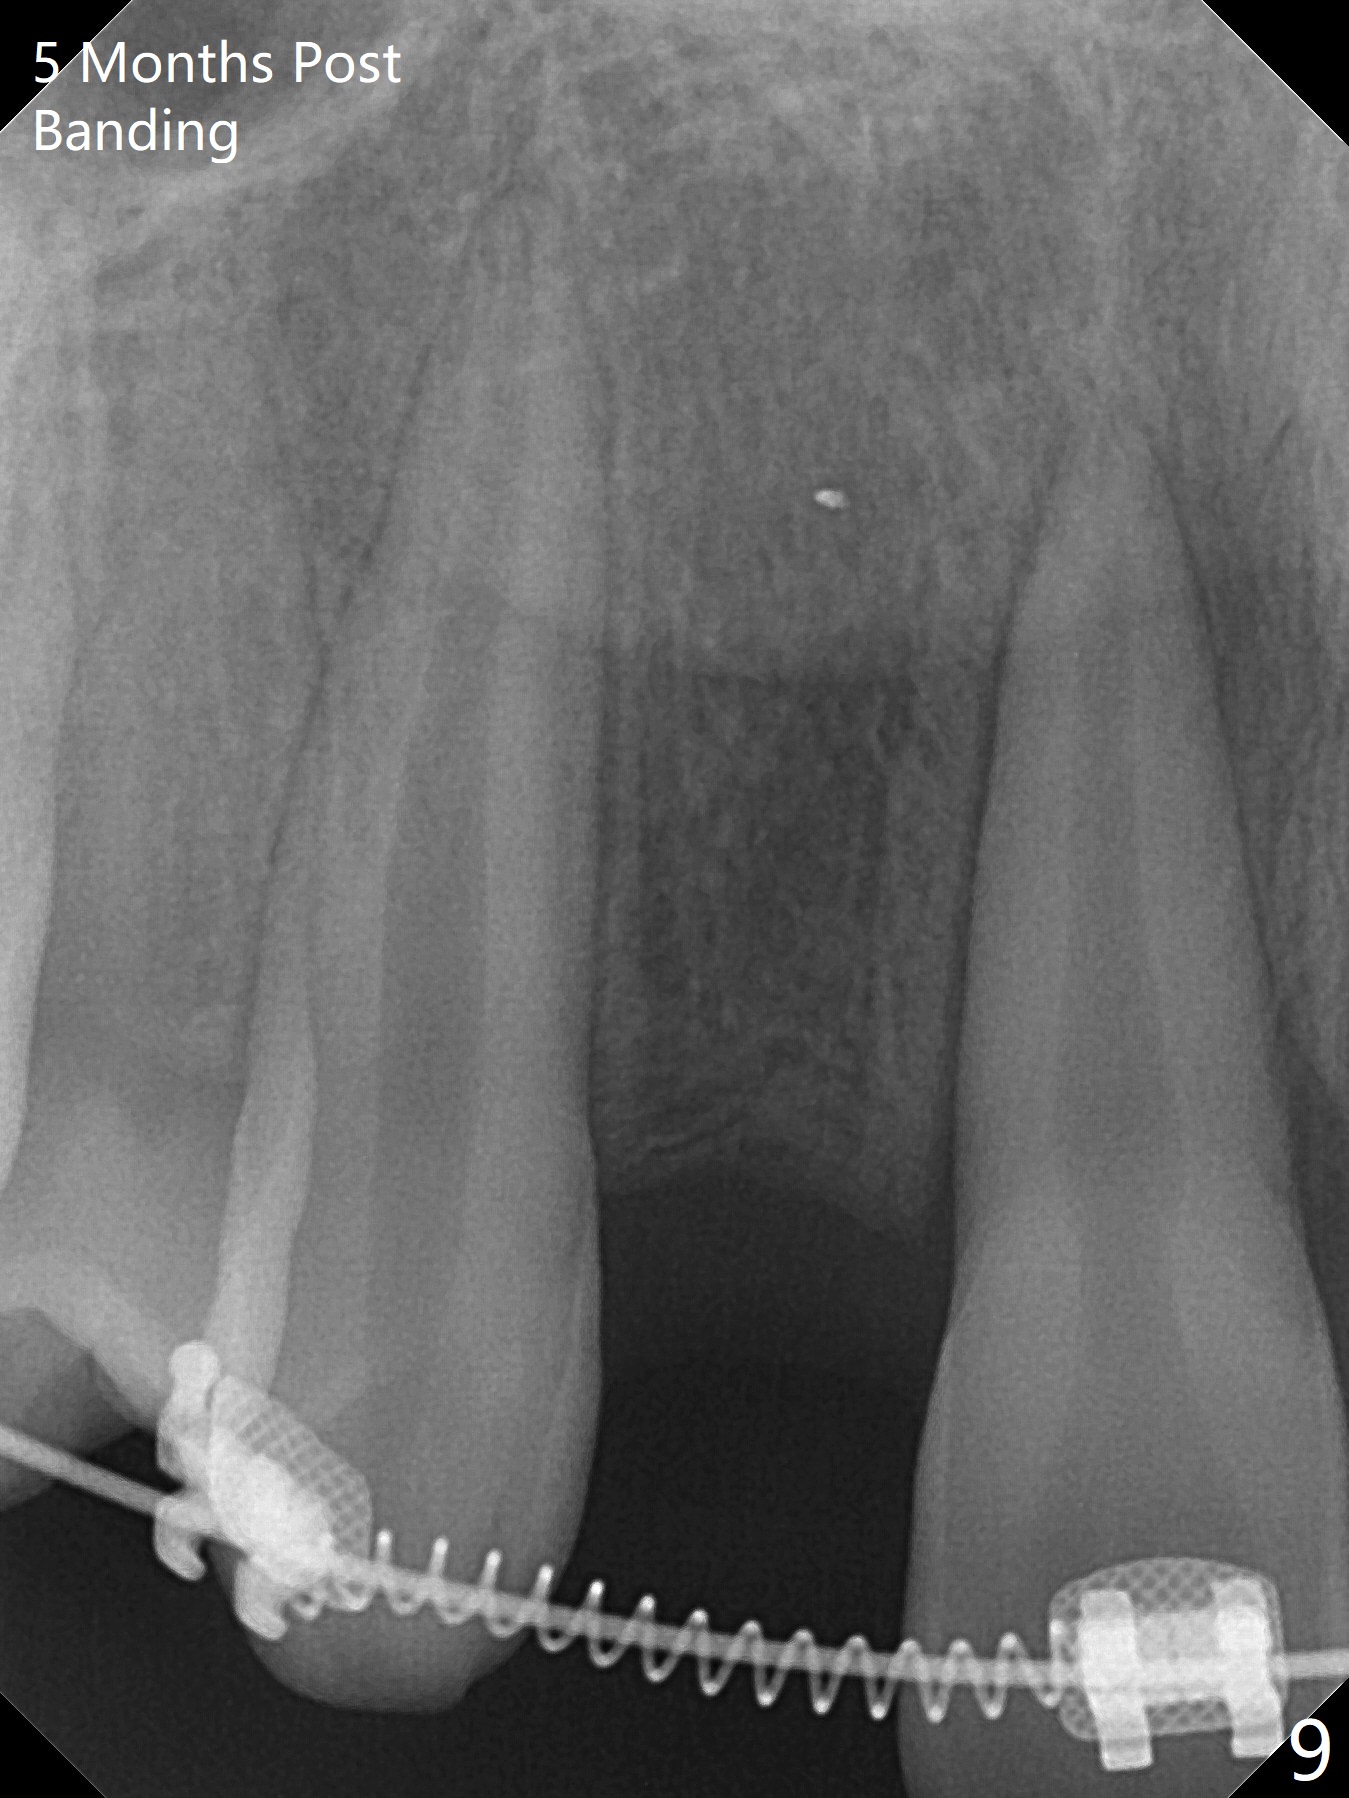

Preop cephalometric tracing shows normal skeletal relationship (Fig.1,2). The upper dental midline deviates to the right (Fig.3). To control root torque, UR1,3 bracketing is intentionally placed off (Fig.4,5, as compared to Fig.6). Take PA for UR1/3 next visit. In fact PA has not been taken. The patient has complained of UR1 turning (mesial incisal edge elongation due to bracket off placement) since the 1st appointment post banding. On the 3rd appointment (2 months 12 days post banding with 18 ss wire), the mesial incisal edge of UR1 and the distal incisal edge of UR3 are trimmed; 18 wires are reused with addition of an open coil spring between UR1-3 (Fig.7). Extra diastemata have appeared mesial and distal to UL1 (Fig.8 *), creating room to correct the upper dental midline shifting. PA is taken 5 months post banding (Fig.9). The roots of neighboring teeth are parallel with new bone formation behind. The mesiodistal space is similar to that of the tooth #10 following consolidation of diastemata on the left. More space is gained 12 months post banding (Fig.10).